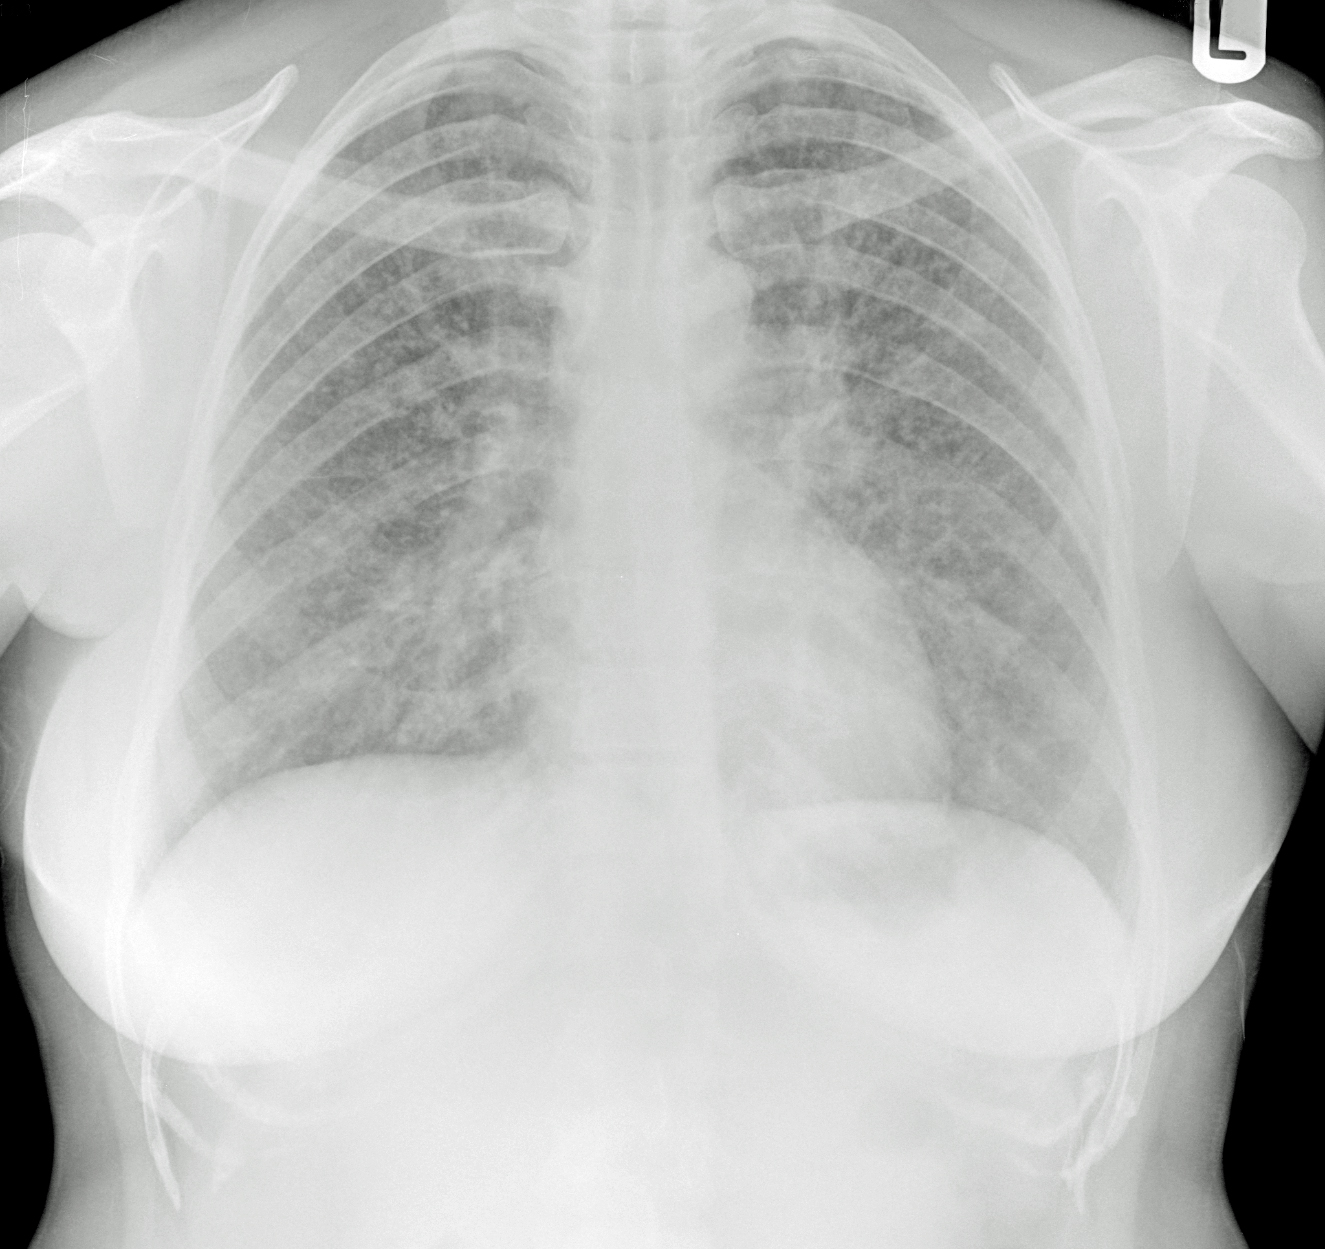

Снимок легких при туберкулезе является важным методом диагностики этого заболевания. На рентгеновских снимках можно увидеть изменения в легких, которые свойственны туберкулезу.

Диссеминированный туберкулез на рентгенограмме

Диссеминированный туберкулез рентген

Диссеминированный туберкулёз лёгких рентген

Диссеминированный туберкулез

Милиарный диссеминированный туберкулез

Фотографии снимков легких при туберкулезе

В данной статье представлены многочисленные фотографии снимков легких при туберкулезе, чтобы помочь вам понять, как выглядят изменения легких на рентгеновских снимках при этом заболевании.